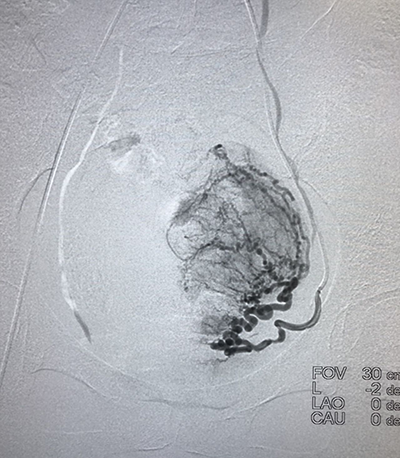

吉林省腫瘤醫(yī)院介入中心建筑面積2200平方米,開放床位35張。擁有UNIQ FD20C 血管造影機?,F(xiàn)有主任醫(yī)師1名,副主任醫(yī)師1名,主治醫(yī)師2名,醫(yī)師2名。(其中博士1名,碩士4名)??剖易?992年開展腫瘤介入微創(chuàng)的診療工作,30年以來,開展了肝癌、肺癌、肝轉(zhuǎn)移癌、肺轉(zhuǎn)移癌、膽管癌、消化道腫瘤、泌尿系統(tǒng)腫瘤、骨轉(zhuǎn)移瘤、盆腔腫瘤等各種良、惡性腫瘤的微創(chuàng)介入手術(shù)2萬余例(包括腫瘤動脈灌注化療栓塞術(shù)、微波消融術(shù)和125I放射粒子植入術(shù)(病種包括:肝癌、肝轉(zhuǎn)移癌、肺癌、肺轉(zhuǎn)移癌、骨轉(zhuǎn)移癌、腎上腺轉(zhuǎn)移癌等)、子宮肌瘤及肌腺癥栓塞術(shù)、經(jīng)皮穿刺骨水泥注射椎體成形術(shù)、食管、膽管狹窄支架置入術(shù)、各部位腫瘤急性出血的栓塞止血術(shù)、胃腸營養(yǎng)管、腸梗阻導(dǎo)管植入術(shù)等)。在國內(nèi)外首先提出低功率消融的治療理念,經(jīng)過1000余例臨床手術(shù)證實,療效確切,無并發(fā)癥,得到了國內(nèi)外同行的廣泛認(rèn)可,并在全國逐步推廣。2011年在國內(nèi)外率先開展三氧化二砷聯(lián)合局部微創(chuàng)介入治療中晚期肝癌的隨機對照研究,提出了早期全身干預(yù)與局部治療的序貫療法,取得了明顯的成績,經(jīng)過中位60個月隨訪期,治療組明顯優(yōu)于常規(guī)對照組,中晚期肝癌的5年生存期達到38.2%,達到了國際領(lǐng)先水平。在國內(nèi)率先開展了多項靶向藥及免疫治療聯(lián)合介入微創(chuàng)治療肝癌、肺癌等臨床研究,取得了較好的成績。在科研方面,共發(fā)表SCI及核心期刊論文100余篇;2019年度獲吉林省科技進步二等獎1項,吉林省科技進步三等獎1項,2014年獲長春市科技進步二等獎1項??剖覟榧质】拱﹨f(xié)會介入治療專業(yè)委員會主委單位,主辦國家級及省級學(xué)術(shù)會議10余次。

(介入術(shù)中操作)(肝癌的介入治療)